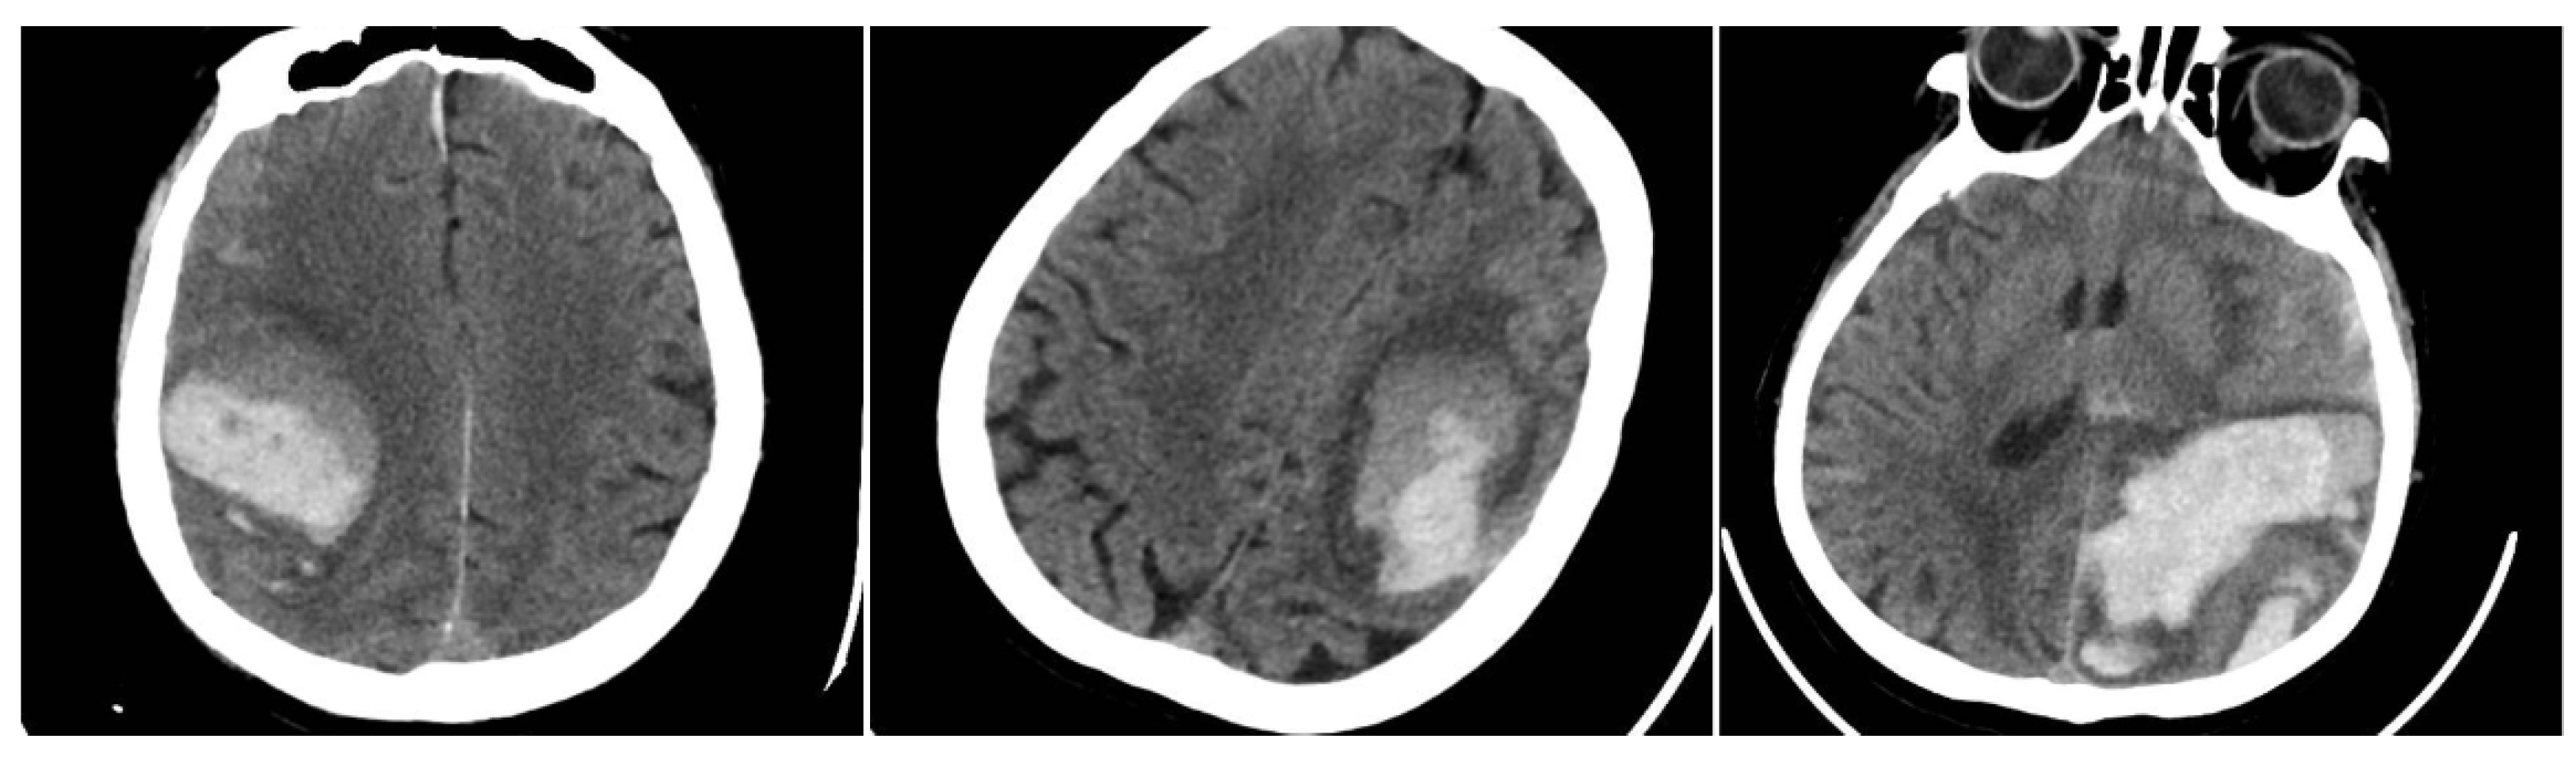

The Blend Sign (BS) was recorded when a well-defined hypoattenuating region directly abutted a hyperattenuating area within the same hematoma, differing by ≥18 HU, without the hypodense portion being fully encapsulated by the hyperdense region (BS = 1 if present, otherwise 0) (Figure 1) [9].

Figure 1. (Left) Hematoma showing Black Hole and Blend Signs; (middle and right) other examples of Blend Signs.

The Black Hole Sign (BHS) refers to a discrete, well-defined hypoattenuating region fully enclosed within a hyperdense clot with ≥28 HU difference and no continuity with normal parenchyma (BHS = 1 if present, otherwise 0) (Figure 2) [10].

Figure 2. Black Hole Sign (BHS)—three examples from our cohort.